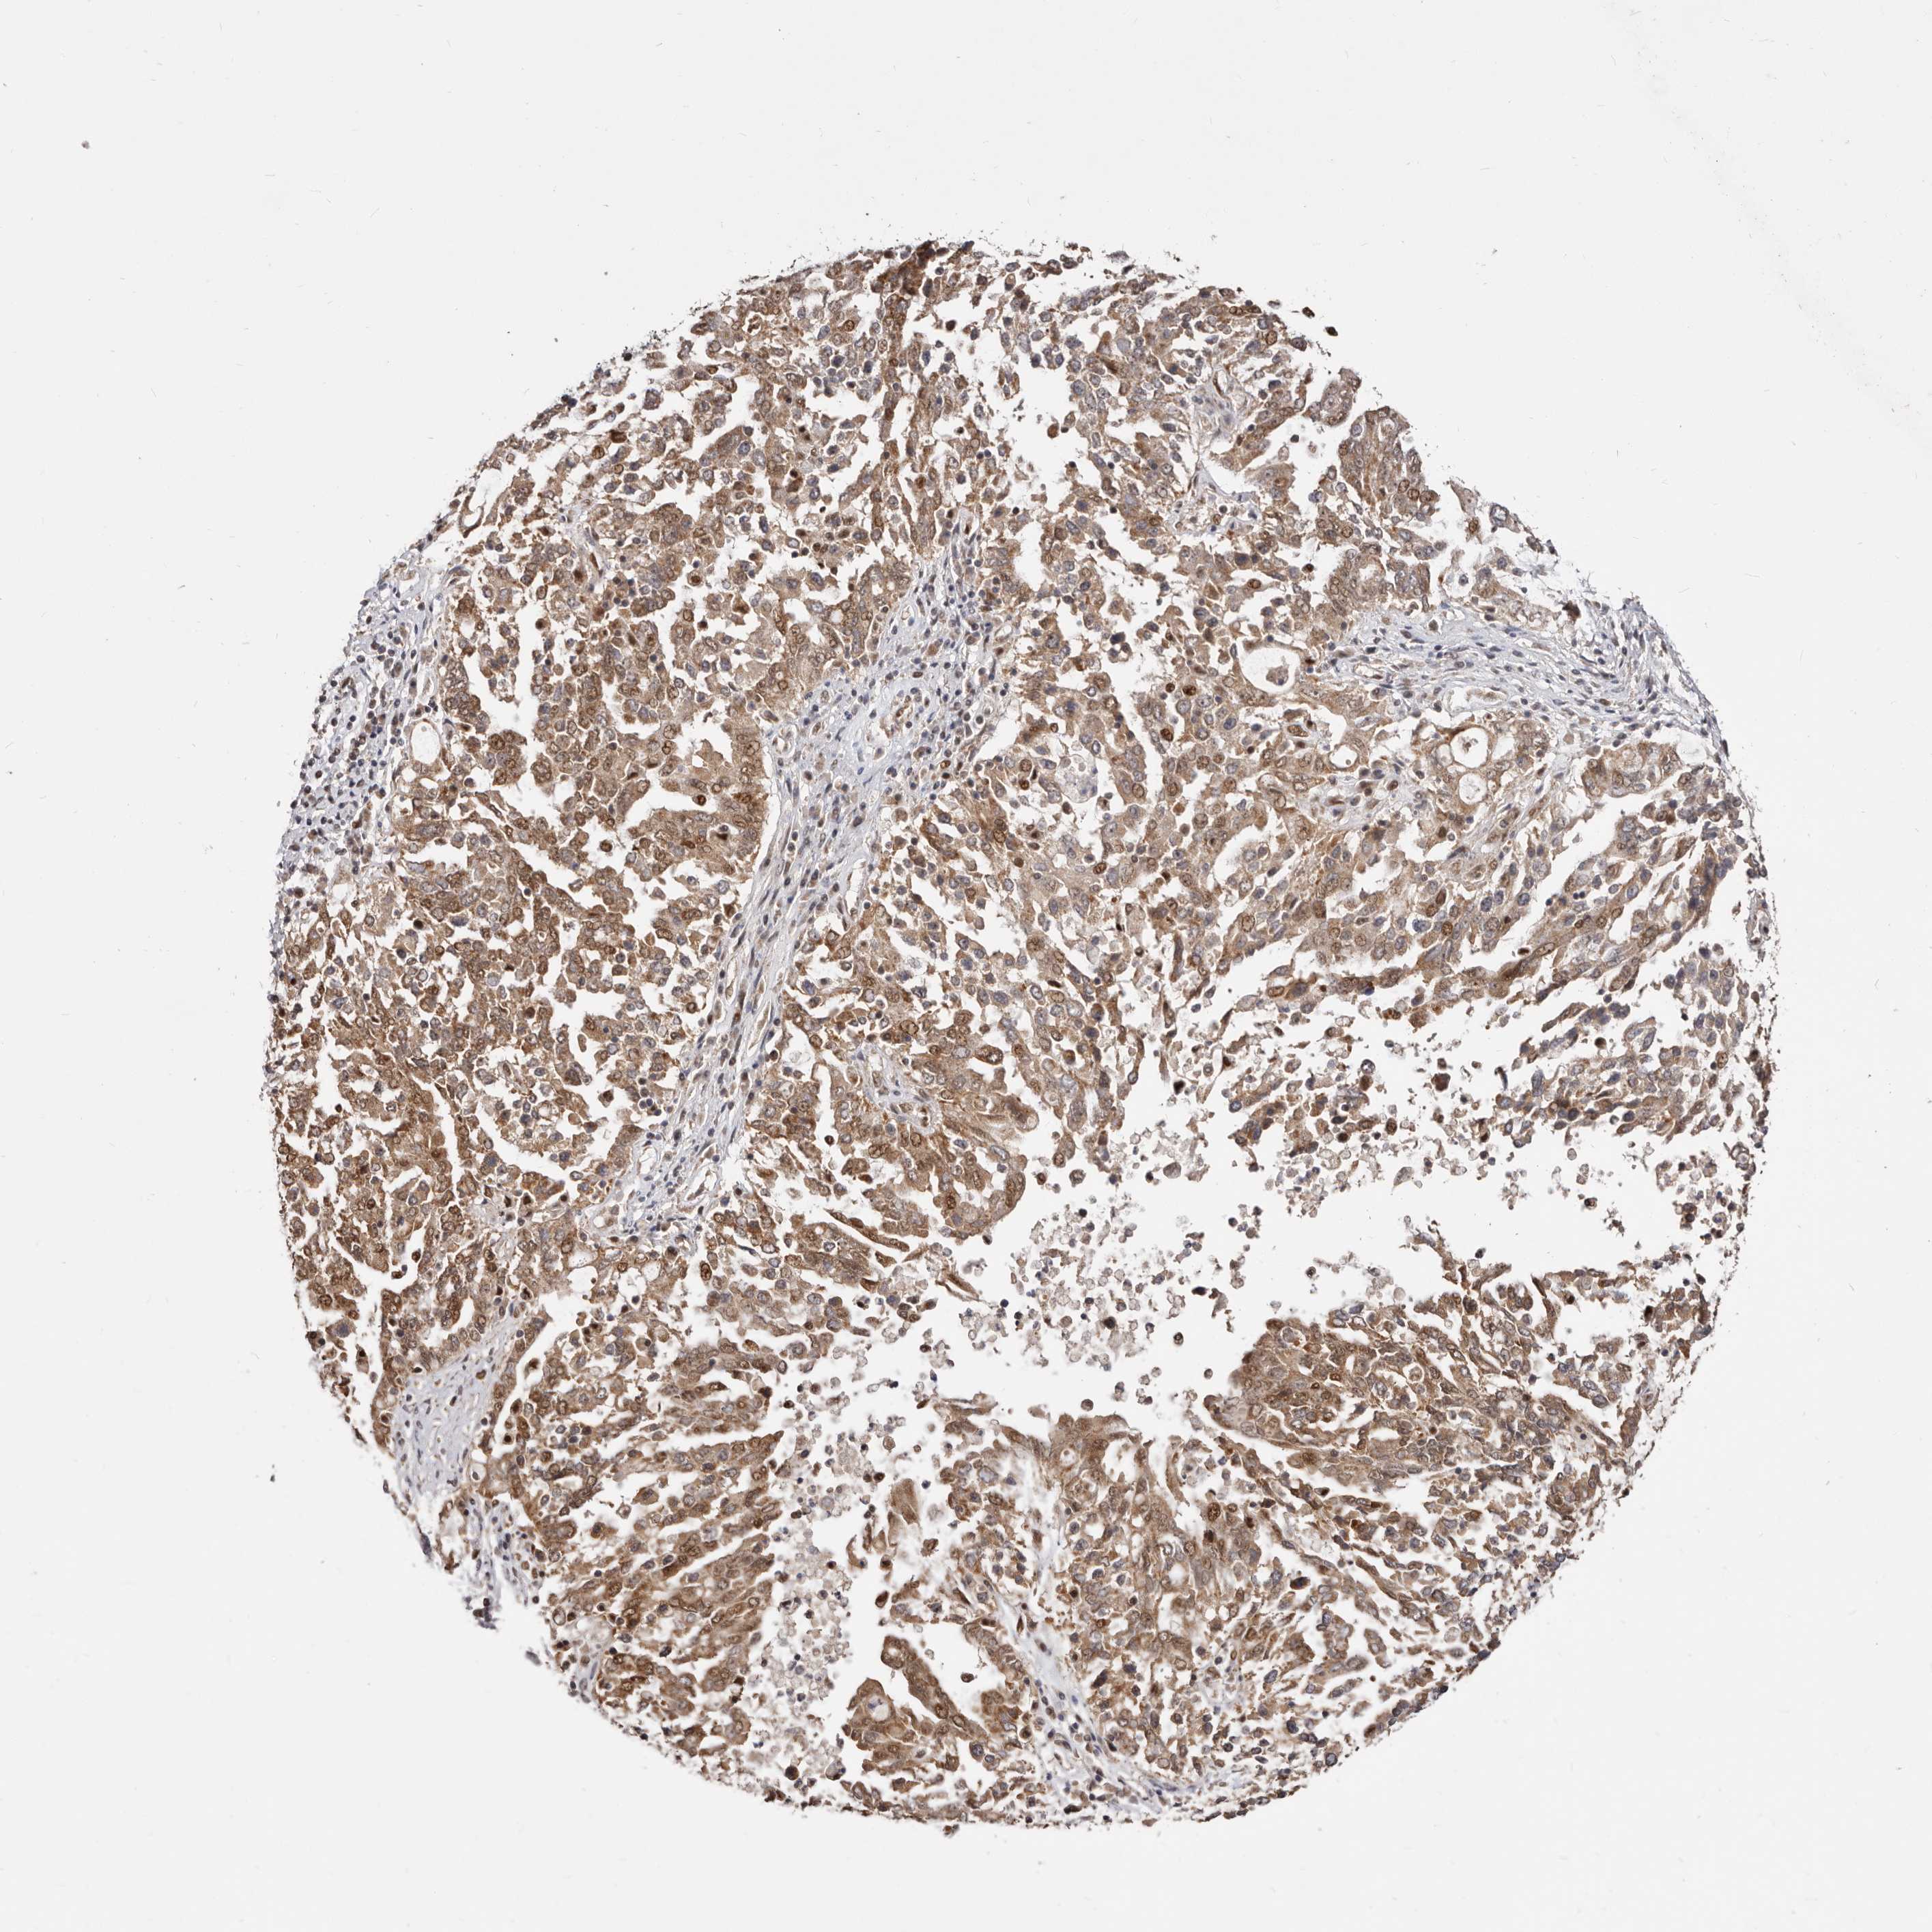

OVARIAN CANCER - Protein expressioni

A mouse-over function shows sample information and annotation data. Click on an image to view it in a full screen mode. Samples can be filtered based on level of antibody staining by selecting one or several of the following categories: high, medium, low and not detected. The assay and annotation is described here.

Note that samples used for immunohistochemistry by the Human Protein Atlas do not correspond to samples in the TCGA dataset.

Antibody stainingi

Antibody staining in the annotated cell types in the current human tissue is reported as not detected, low, medium, or high, based on conventional immunohistochemistry profiling in selected tissues. This score is based on the combination of the staining intensity and fraction of stained cells.

Each image is clickable and will lead to virtual microscopy that enables deeper exploration of all samples and also displays staining intensity scores, fraction scores and subcellular localization as well as patient and tissue information for each sample.

Antibody HPA021463

High

Medium

Intensity

Strong

Quantity

>75%

Location

Nuclear

Cytoplasmic/membranous

Cytoplasmic/membranous,nuclear

Cystadenocarcinoma, serous, NOS